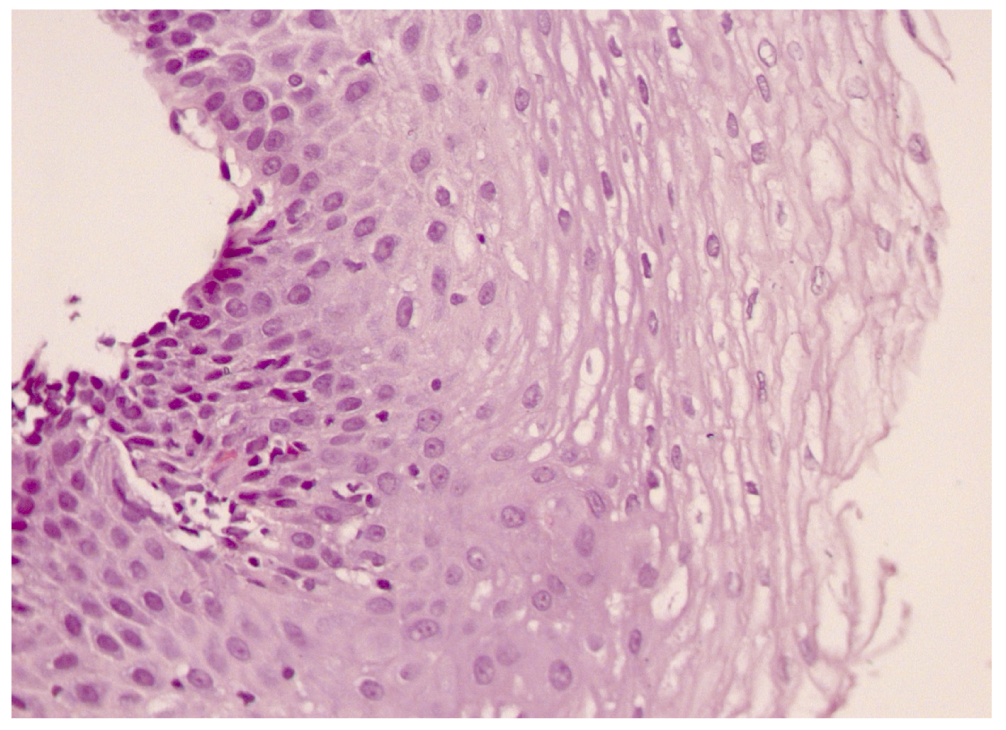

Принимая во внимание отсутствие эффекта от проводимой терапии, при повторном эндоскопическом обследовании проведена биопсия слизистой оболочки пищевода. Морфологическая картина (30.06.2014): плоский эпителий смотрится раздражённым, стратификация отсутствует. Большое количество интраэпителиальных эозинофилов (>20 в поле зрения). Подэпителиальные ткани с явлениями склероза, вероятными лимфоэктазами и эозинофильной инфильтрацией (эозинофильный эзофагит) (рис. 1).

Рис. 1. Гистологическая картина слизистой оболочки пищевода до лечения.

Fig. 1. Esophageal mucosa before treatment.